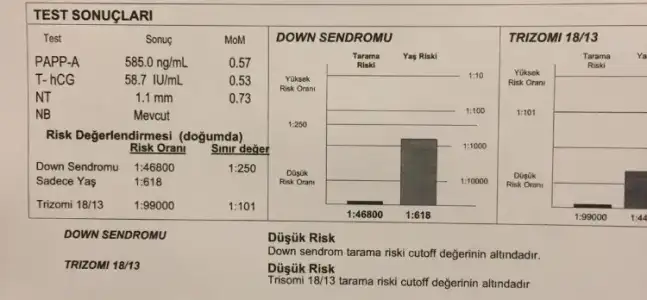

aynen öyle detaylida hicbir down sendromu belirtisine rastlamadim dedi doktorumda.Ben bugün gittim ikili test için kan verdim, foktor usg baktı cinsiyeti kesin olarak 20. Haftada söylecekmi

Canım ikili test sonucu için hiç üzülme, oranı yüksek çıkıp sağlıklı bebekleri olan o kadar çok insan var ki. Nifty testi yaptır sonuç ikili teste göre daha güvenilirdir.

Benim dpktorum şuan herşey çok güzel gifiyor, inşallah böyle devam eder. İkili test sonucu çıkınca da konuşuruz ama çok doğru sonuç vermiyor sanırım ki amniyosentez yaptırabiliriz istersen dedi.